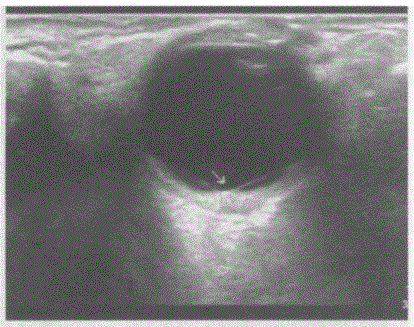

问题 临床资料:男,57岁,自诉近视30余年,近1月右眼视物模糊,眼前阴影遮挡,视力下降,当地医院诊断糖尿病视网膜痛变。眼科检查:视力:右0.05、左0.6。眼底右眼窥视较模糊,视盘边界不清,水肿,血管走行尚可,视网膜大量散在点片状出血,火焰状。 超声综合描述:右眼玻璃体暗区内可见带状回声,其尖端与视盘相连,两边分别与周边球壁相连(箭头所示),呈"V"形,运动试验、后运动阳性,CDFI:带状回声内可见动脉血流信号,且与视网膜中央动脉血流信号相延续。 超声提示:

选项 A.玻璃体后脱位 B.脉络膜脱离 C.视网膜脱离 D.玻璃体浑浊

答案 C